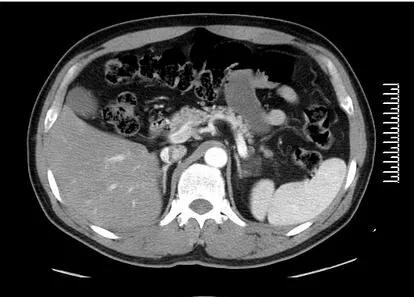

后来一家体检机构做体检,发现尿液中有蛋白一个+号;机器测量血压140/80毫米汞柱,似乎并不高。拿着体检机构的检查单,看了一个肾内科门诊,门诊医生手工测量却发现血压190/70mmH,心跳在110次/分;考虑存在高血压,蛋白尿是由于血压升高导致。彩超发现肾上腺有肿块,考虑嗜铬细胞瘤,抽血检查其他指标,最终确诊为继发性高血压由嗜铬细胞瘤所引起。

1)嗜铬细胞瘤。是一种神经内分泌肿瘤icon,可以引起阵发性头痛发汗,心动过速以及伴有血压升高;其引起的血压多为阵发性的升高,并且比一般原发性的高血压水平要高,但是也有百分之5~15%的病人血压是正常的。肿瘤切除后血压可以恢复正常。